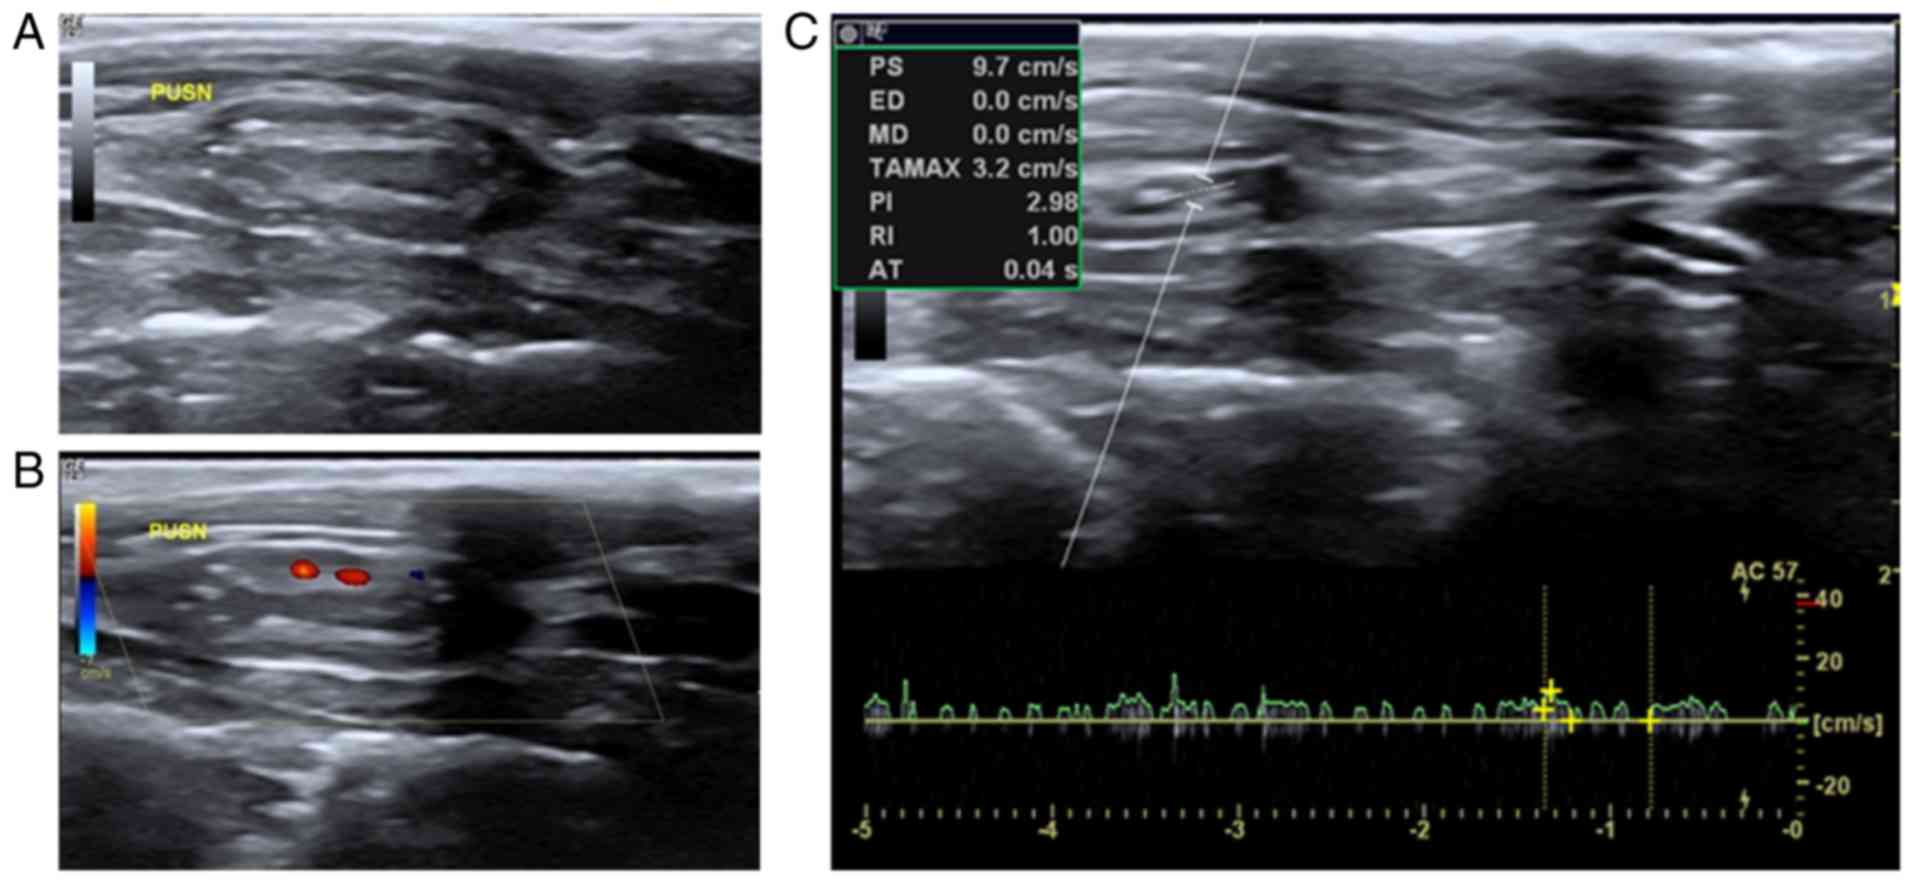

DC ENaC-Dependent Inflammasome Activation Contributes to, Accurate and continuous ultrasonography evaluation of small,

Accurate and continuous ultrasonography evaluation of small, Protein acylation: mechanisms, biological functions and